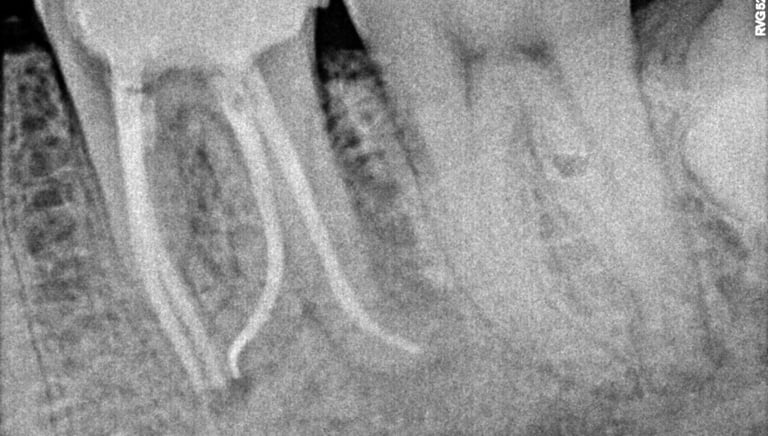

Root Canal Treatment near Shyamal, Ahmedabad

Before

After

All images shown here represent real clinical cases treated at our dental clinic with patient consent.

At Shree Dental Care, we focus on gentle, precise, and well-planned root canal treatment to remove infection, relieve pain, and preserve your natural tooth structure.

Patients from Shyamal and nearby areas of Ahmedabad visit our clinic for comfortable root canal procedures carried out using modern techniques and strict hygiene protocols. The treatment helps eliminate infection from inside the tooth, prevents further damage, and restores normal chewing function.